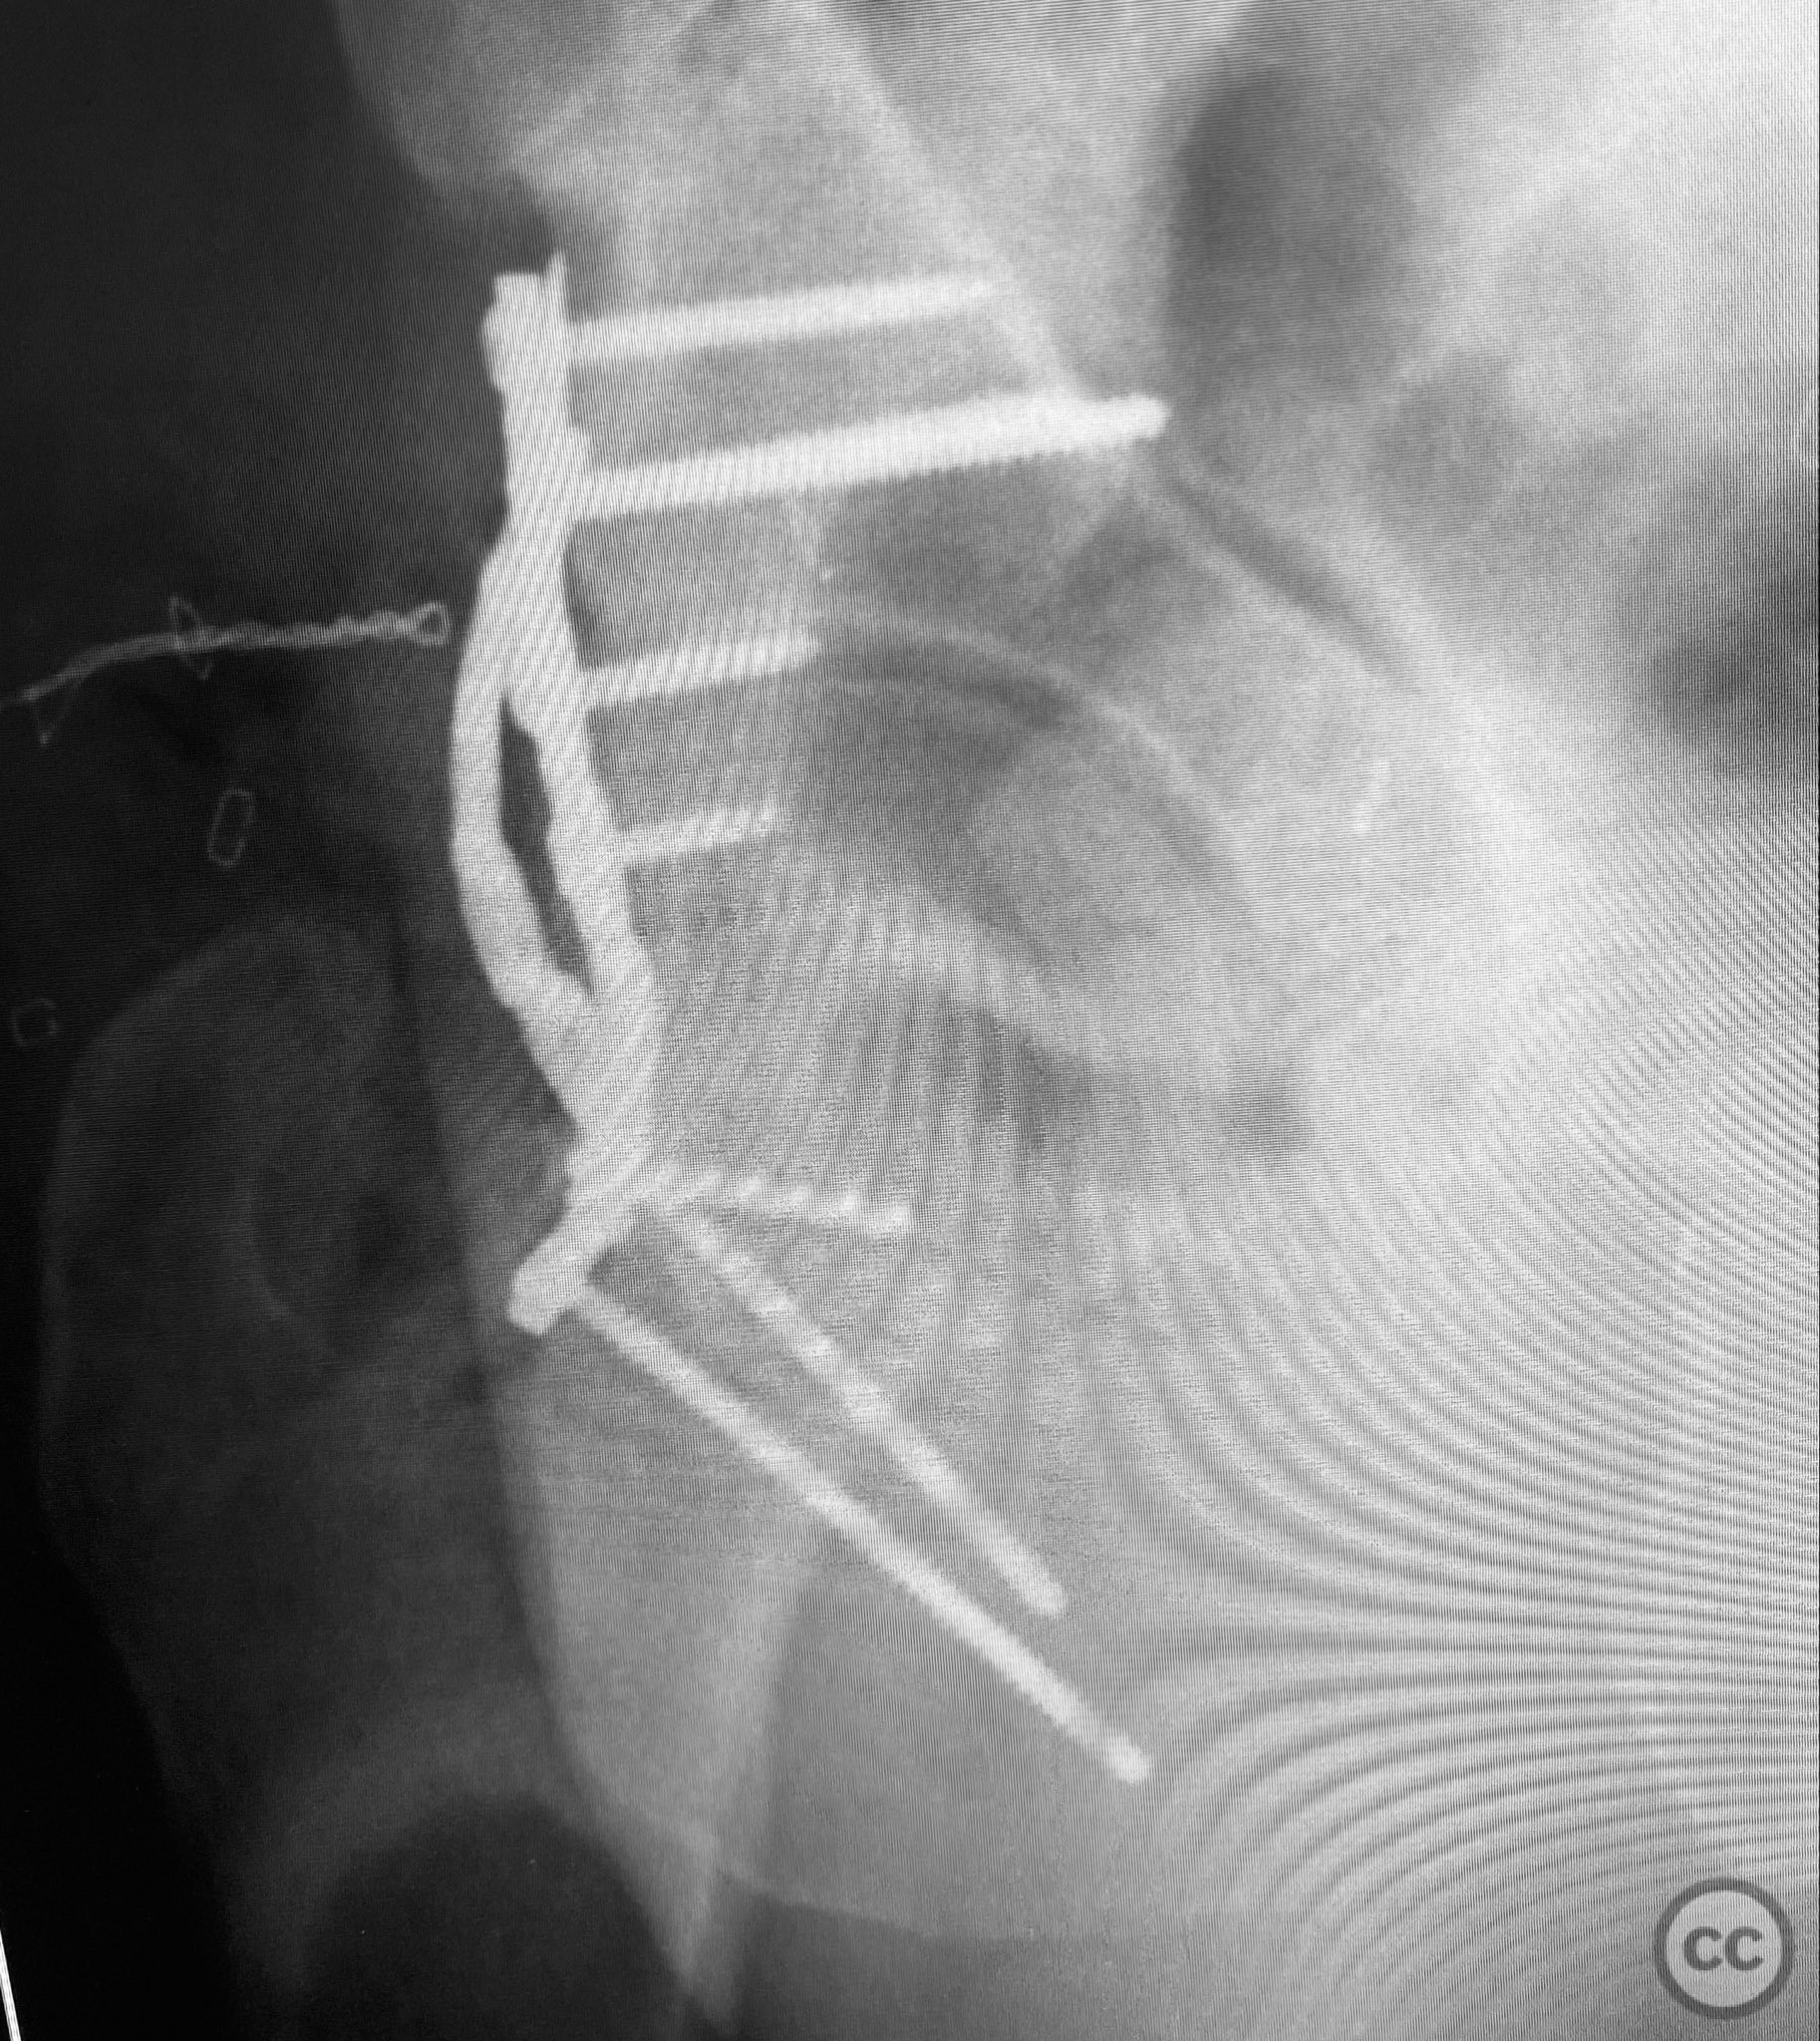

Anatomical surgical approach:  A standard Kocher-Langenbeck approach was performed: a longitudinal incision centered over the greater trochanter, extending proximally along the posterior iliac crest and distally along the femoral shaft. The fascia lata was incised, and the gluteus maximus split in line with its fibers. The short external rotators and piriformis were identified, tagged, and released to expose the posterior column and wall of the acetabulum. The sciatic nerve was identified in the greater sciatic notch region; intraoperatively, it was found to be severely contused, displaced, and uniquely penetrated by a sharp posterior wall fragment. Neuroplasty was performed, freeing the nerve from impalement and surrounding scar tissue. The intra-articular fossa acetabuli fragment was extracted, anatomically reduced, and stabilized along with other posterior wall fragments. A spring hook plate was applied to secure the cranial wall fragment due to its size and comminution.

Operative remarks:

Intraoperatively, the sciatic nerve was found to be not only contused but also impaled by a displaced posterior wall fragment—a rare occurrence in acetabular trauma. Careful neuroplasty was required to release the nerve from direct bony penetration without further iatrogenic injury. Reduction of all articular fragments was achieved under direct visualization, with particular attention to restoring congruity of the acetabular rim and fossa. The use of a spring hook plate provided necessary buttress for the large cranial wall fragment, which could not be adequately stabilized with standard plating alone.

Orthopaedic implants used:   3.5mm reconstruction plate, spring hook plate